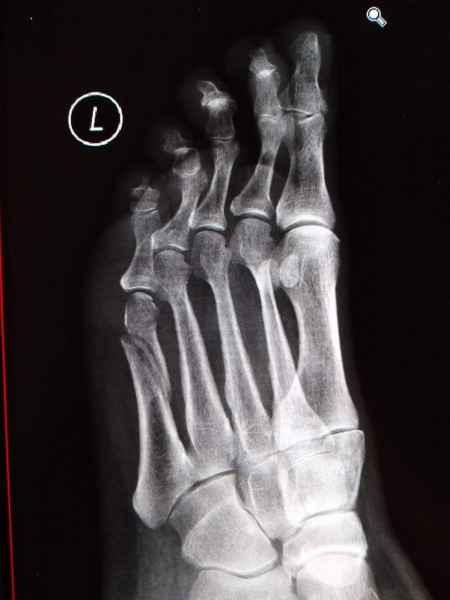

El pie es el órgano distintivo y característico de la especie humana, la única criatura que marcha erguida. El pie es una muy compleja estructura de arquitectura perfecta, adaptado a su función de apoyo, traslación, salto, con una riquísima sensibilidad que le permite detectar las más leves imperfecciones del suelo para estabilizar la marcha.

Tanto la estructura del pie como su funcionalismo que es la marcha, pueden ser asiento y manifestación respectivamente de alteraciones locales ó sistémicas, por lo que su cuidadoso examen resulta de extrema utilidad diagnóstica.